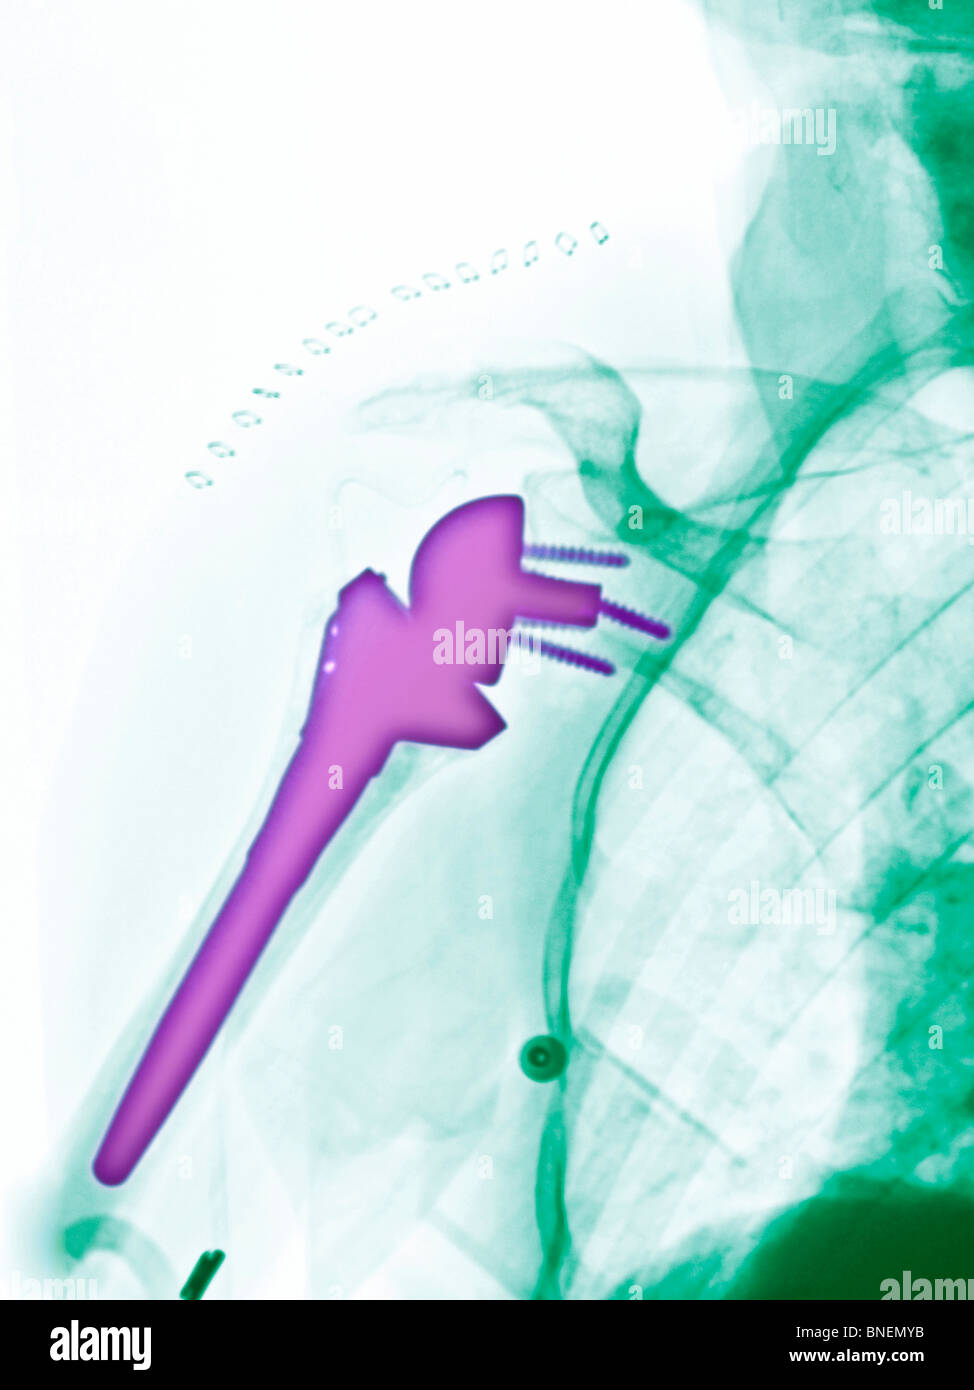

From www.alamy.com

xray showing a shoulder replacement Stock Photo Alamy Shoulder Replacement X Rays This article is chiefly limited to the routine radiographic evaluation of shoulder arthroplasties and guidelines to. shoulder replacement removes damaged areas of bone and replaces them with parts made of metal and plastic (implants). shoulder arthroplasty is the primary treatment of advanced glenohumeral arthritis once conservative measures fail, can restore function to. shoulder arthroplasties are a common. Shoulder Replacement X Rays.

xray showing shoulder replacement Stock Photo Alamy Shoulder Replacement X Rays This article is chiefly limited to the routine radiographic evaluation of shoulder arthroplasties and guidelines to. They can show loss of the normal joint space between bones, flattening or irregularity in the shape of the bone, bone spurs, and loose pieces of cartilage or bone that may be floating inside the joint. Reverse shoulder arthroplasty, total shoulder. shoulder arthroplasties. Shoulder Replacement X Rays.

xray showing a shoulder replacement Stock Photo Alamy Shoulder Replacement X Rays shoulder arthroplasty is the primary treatment of advanced glenohumeral arthritis once conservative measures fail, can restore function to. the most common indications for shoulder arthroplasty are osteoarthritis, inflammatory arthritis, proximal humerus fractures, irreparable. They can show loss of the normal joint space between bones, flattening or irregularity in the shape of the bone, bone spurs, and loose pieces. Shoulder Replacement X Rays.